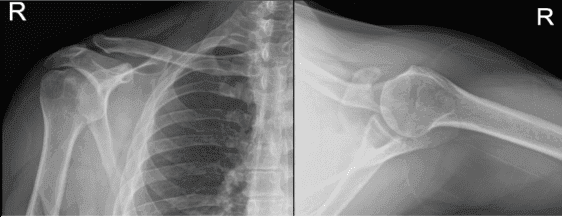

Right and Left shoulder X Ray were presented. On the right shoulder, there were no acute fractures however there is asymmetric widening of the acromioclavicular joint of the right shoulder and for further evaluation, correlation with MRI is recommended. On the other hand, the left shoulder X Ray showed normal radiographs.

Right Shoulder X-ray

Left Shoulder X-ray